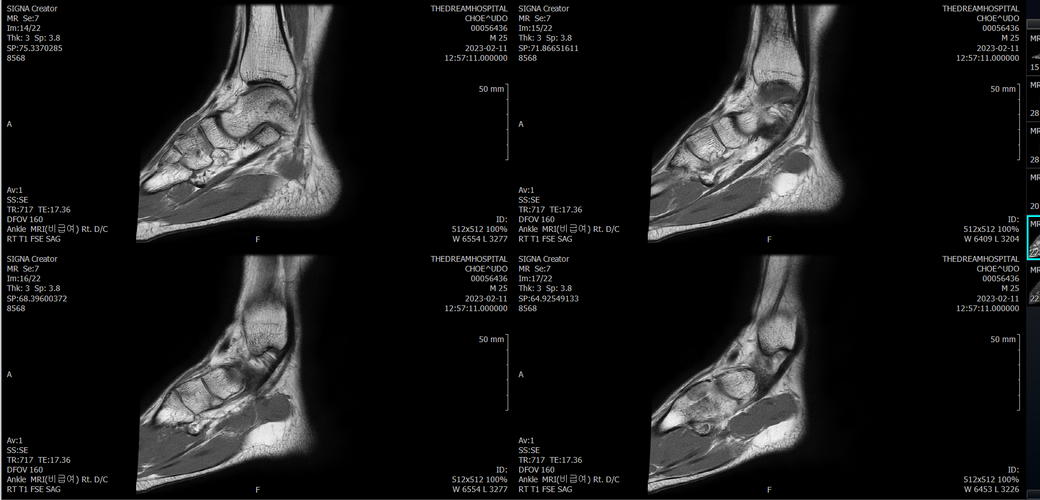

우선 전반적으로 봤을 때 큰 이상은 없어보입니다.

전거비인대 등도 저명한 손상은 없는 것 같아 보이지만, 어느 부분의 통증 등으로 인해 촬영을 하셨는지 말씀을 해주신다면 보다 정확한 병변파악이 가능하겠으며, 병원에서 판독이 완료되신다면 전화 등으로 문의를 해보시는 것이 좋겠습니다.